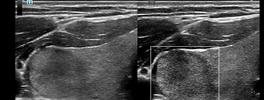

Liver Elastography